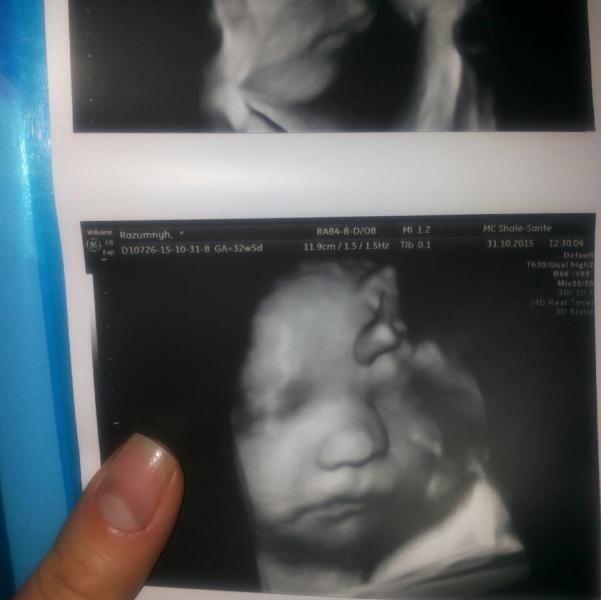

Ой, девочки!!!!!! Была вчера на УЗИ в шале санте, сказать что я в восторге= ничего не сказать!!!!! Врач- генетик Павленко, потрясающий доктор и человек!!!! Развеяла все мои страхи, по поводу преждевременных родов, посмотрела шейку, не нашла причину болей в животе, сказала, что причина болей явно не имеет отношения к беременности, значит это все таки кишечник! Мой малыш в полном порядке, вес 2100 гр, развивается в срок 32-33 недели))))) теперь новости из не самого приятного, плацента не поднялась на 17 мм выше зева и это плохо, скорей всего будет ПКС и мой малыш сидит на попе..... умеренное многоводье, надеюсь что перевернется как надо!!!!!

да, врач и 3 д включила, и кучу фоток сделала, диск записала)))))доплер, все очень подробно рассказала, даже по моей личной просьбе, шейку посмотрела! и все это за 2100! после того как я была в зимамеде, не думала что, что-то лучшее есть, я имею ввиду аппарат!

Какой красивенький малыш!!! Фото супер!!! Теперь я еще больше хочу поехать в эту клинику на узи